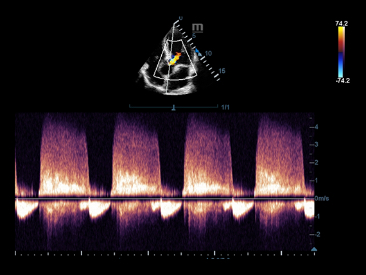

Многофункциональная система DC-60 Exp с X-Insight представляет собой комплексное решение, которое помогает управлять повседневной клинической практикой с легкостью и уверенностью.

Основываясь на глубоком понимании потребностей клиентов, компания Mindray разработала систему DC-60 Exp с X-Insight, чтобы обеспечить высокую производительность и точность визуализации вкупе с наглядностью, исключительной интеллектуальностью и огромным опытом.